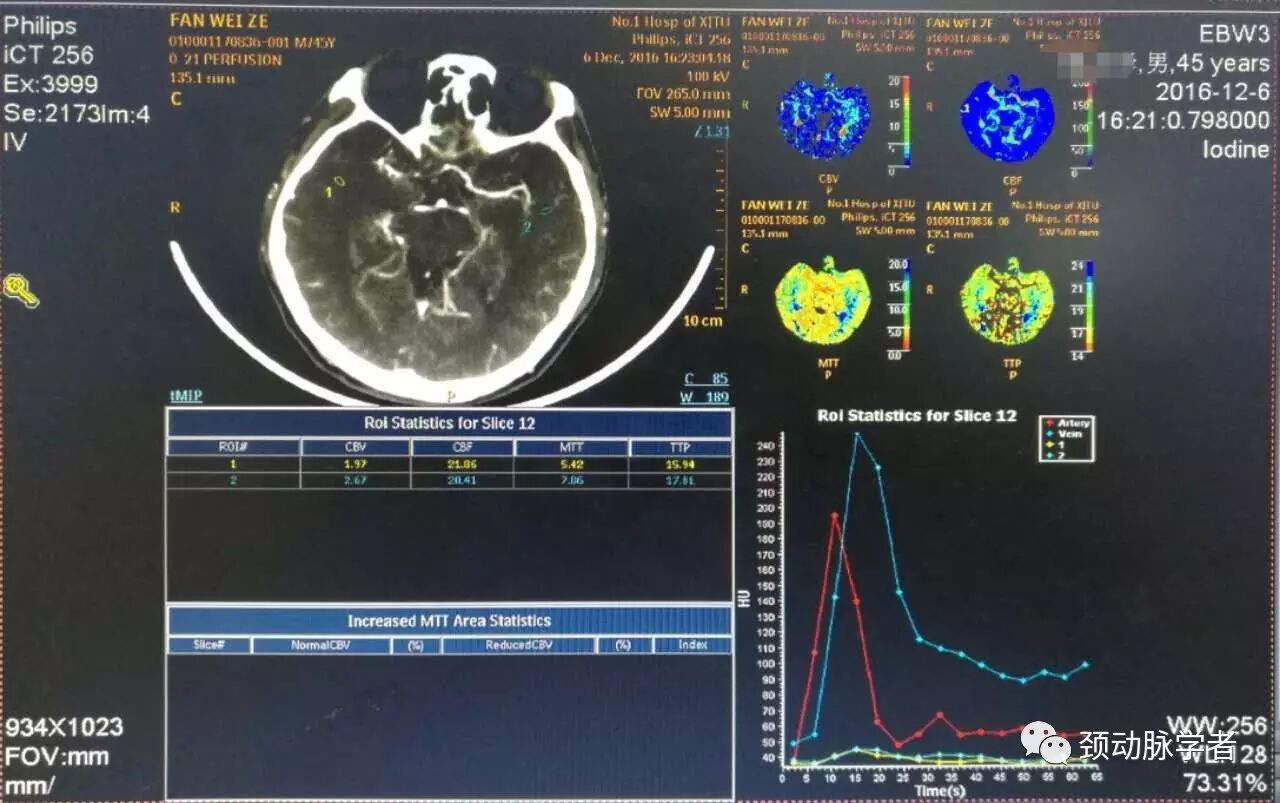

头颅CTP显示,与DSA相符,双侧大脑半球明显缺血,解决左颈内动脉床突上段99%狭窄获益最大!但风险也大!